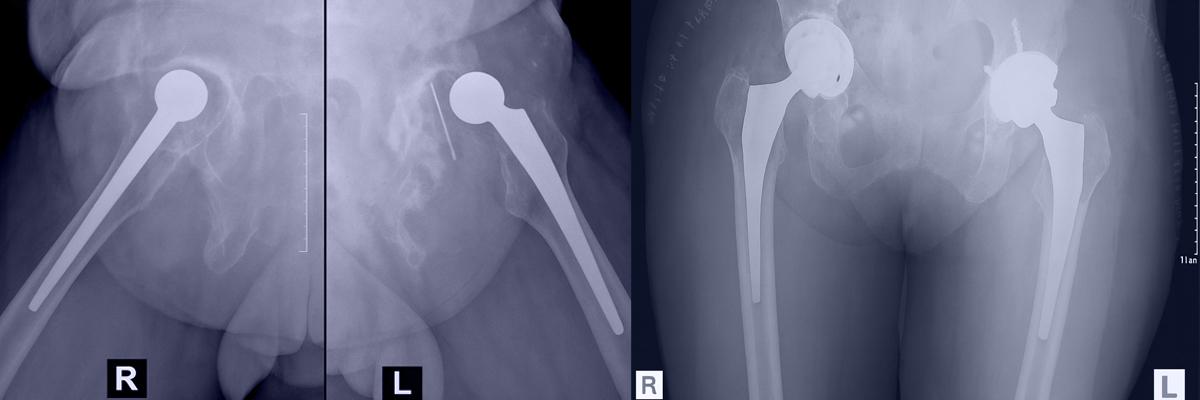

Revision Hip Replacement

Revision Hip Replacement involves removing a previously implanted artificial hip joint and replacing it with a new, customised implant to restore joint function and reduce pain or instability.

During revision, some bone loss may occur in the acetabular region and proximal femur. In many cases, the abductor muscle mechanism is also compromised. Implant selection—including cup design, liner, stem length, head size, and bearing surface—is tailored based on these structural changes.

Revision hip surgery often requires a spectrum of implants and tools such as long stems, acetabular augments, cemented stems, cables, and specialised reconstruction components—prepared in advance for intraoperative flexibility.